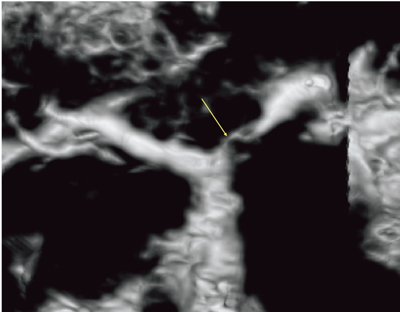

Cavity(USCP)で肝門部を中心に再構成した画像では,左肝管の根部の狭小化が確認できた(図4)。Fly Thruでは,下部胆管から肝門部に向かって視点を移動させ,肝管合流部から左肝管,前区域枝,後区域枝に入ろうとすると,左肝管は狭くなって入りにくい部分があり,しかし,そこを抜けると開けて管腔が認識できる(図5)。一方で,前区域枝には入れず,後区域枝には入ることができた。Bモードで狭くなっていた部分は,Fly Thruでは内腔の認識ができなかったと考えられる。管腔臓器を外から見るCavity(USCP)と,中から観察するFly Thruの両方を使うことで,新しい情報が得られると考えられる。

図4 症例2:硬化性胆管炎のCavity(USCP)画像

左肝管の根部が狭小化している(↓)。